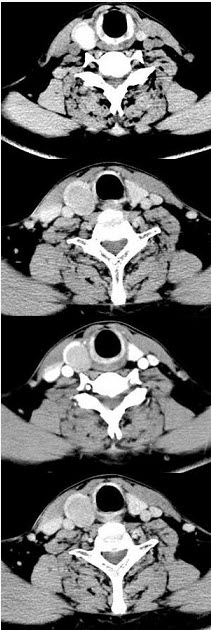

男,43岁,右颈部扪及一包块,CT如图所示,应诊断为()。

A、甲状腺腺瘤

B、甲状腺腺癌

C、结节性甲状腺肿

D、甲状腺原发淋巴瘤

E、甲状腺转移癌

正确答案:

A